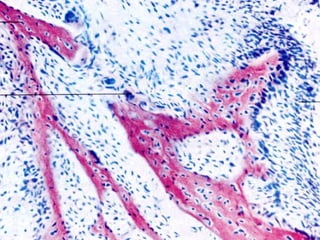

Osteosarcom

11/26/13